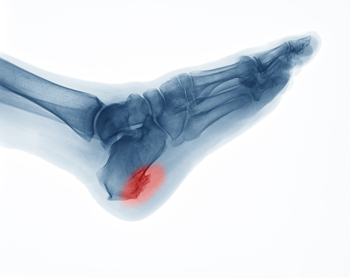

How Did I Get a Heel Spur?

A spur is a bony growth that may develop due to repetitive irritation or stress. As its name suggests, a heel spur develops on the heel bone or calcaneus. More specifically, it typically forms in one of two places on the heel bone. An inferior calcaneal spur forms underneath the heel bone and is associated with plantar fasciitis, a common ligament injury in the foot. A posterior calcaneal spur forms on the back of the heel bone and is associated with Achilles tendonitis. Heel spurs can be asymptomatic or cause sharp pain, dull aches, stiffness, and numbness in the affected heel. Corns and calluses also often form over the affected area. If you have painful heels, please see a podiatrist for a diagnosis and treatment.

Heel spurs are formed by calcium deposits on the back of the foot where the heel is. This can also be caused by small fragments of bone breaking off one section of the foot, attaching onto the back of the foot. Heel spurs can also be bone growth on the back of the foot and may grow in the direction of the arch of the foot.

Older individuals usually suffer from heel spurs and pain sometimes intensifies with age. One of the main condition's spurs are related to is plantar fasciitis.

The pain associated with spurs is often because of weight placed on the feet. When someone is walking, their entire weight is concentrated on the feet. Bone spurs then have the tendency to affect other bones and tissues around the foot. As the pain continues, the feet will become tender and sensitive over time.

How to Treat Heel Spurs

Heel spurs are calcium deposits that cause bone protrusions on the heel bone. Heel spurs are usually associated with plantar fasciitis, which occurs when the plantar fasciitis in the foot becomes inflamed. Typically, heel spurs don’t cause any symptoms. However, they can produce chronic or intermittent heel pain. Those who have had the condition often describe the irritation as a stabbing pain.

There are risk factors that may make you more likely to develop heel spurs. People who have abnormal walking gaits, run and jog on hard surfaces, are obese, or wear poorly fitting shoes are more likely to develop heel spurs.

Fortunately, there are precautions you can take to avoid developing heel spurs. One of the best ways to do this is by wearing well-fitting shoes with shock-absorbent soles. Another preventative technique is to choose running shoes if you plan on running, and walking shoes if you plan on walking. Shoes are made for different activities and it is important to research a shoe before you purchase a pair.

The pain associated with heel spurs often decreases the more you walk. However, a recurrence of pain after an extended period of rest or walking is likely to occur with this condition. Those with severe heel spur pain may opt to go the surgical route for treatment. However, more than 90% of those with the condition get better without surgical treatment. If you have a heel spur and want to know if surgery is right for you, you should go to your podiatrist and he or she will be able to conduct a pre-surgical test or exam to determine if you are an optimal candidate for surgery.